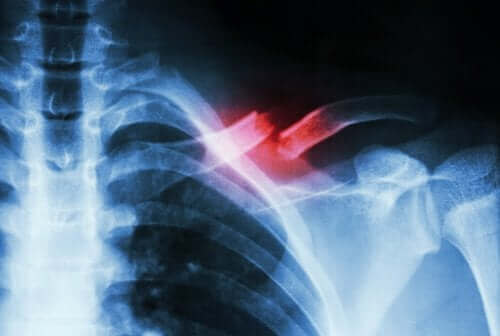

Stres kırığı, kemikte güçlü bir darbe haricinde bir şeyden kaynaklanan küçük bir kırılma olduğunda ortaya çıkar. Tipik olarak, tekrarlayan hareketlerle veya bir aktivitenin miktarında veya yoğunluğunda hızlı bir artışla tetiklenir.

Bu tür kırıkların teşhisi kolay değildir. Bu nedenle, diğer koşullardan ayırt etmek için bir tıp uzmanı ve tamamlayıcı testler gerektirirler. Çünkü kırık genellikle röntgende tespit edilmez.

Stres kırığı, kemikte bir tür şerit veya çatlaktır. Yukarıda söylediğimiz gibi tekrarlanan mikrotravma veya aşırı yüklenme nedeniyle ortaya çıkarlar. Ek olarak, belirli fiziksel aktiviteleri gerçekleştirirken şiddetli bir ağrı açığa çıkarabilirler. Ardından, faaliyetler bittiğinde genellikle bu ağrılar kaybolur.